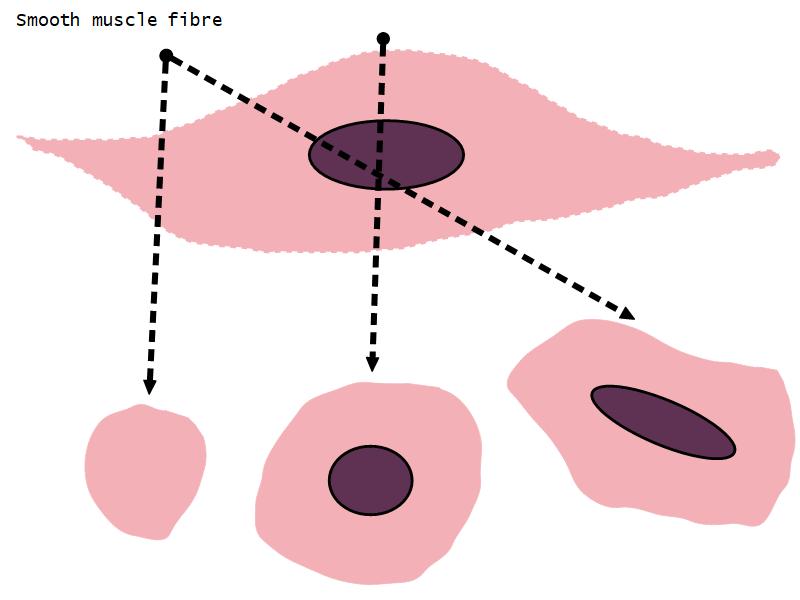

- Interlaced with smooth muscle fibres

- Smooth muscle

- Fibres and bundles